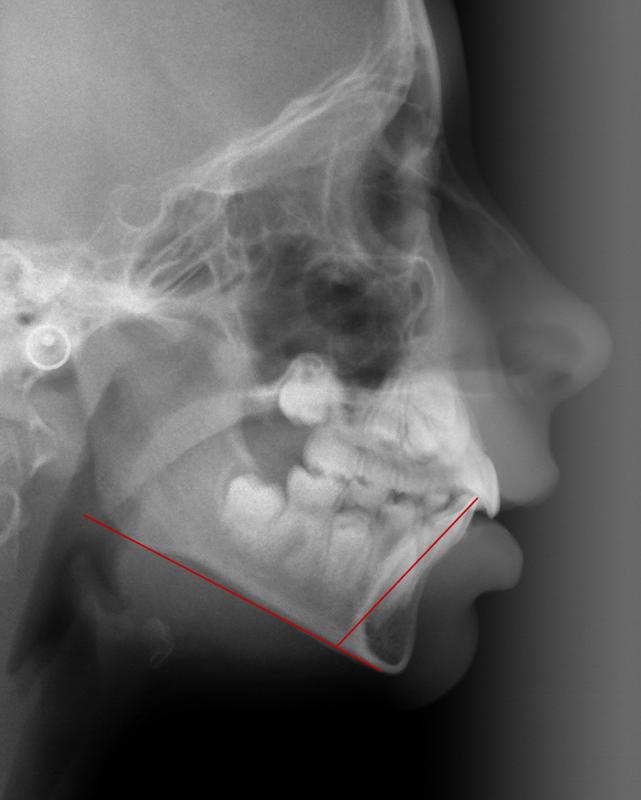

- Finesse, fenestration voire absence d’os en vestibulaire des incisives (sur téléradiographie de profil ou CBCT) (figure 5a et 5b)

Figure 5 : patiente de 38 ans présentant un déséquilibre mécanique de la région incisivo-canine mandibulaire se traduisant par un encombrement incisivo-canin sévère par rétroalvéolie et égression incisive (a), un parodonte fin et une muqueuse libre suivant le relief des racines des incisives (b), et une absence d’os alvéolaire vestibulaire au CBCT (c, d et e).

Vues endo-buccales (a, b, c) et téléradiographie de profil initiales avec IMPA=105° (d);

Téléradiographie de profil initiale, IMPA = 108° (a),

Téléradiographie de profil avant traitement (a),

téléradiographie de profil de réévaluation à 12 mois de traitement multi-attaches montrant l’aggravation de la proalvéolie mandibulaire avec IMPA=110° (b), l’affaiblissement labio-mentonnier est décidé à ce moment,

téléradiographie de profil en fin de traitement après 9 mois de finitions sur multi-attaches et 1 an de contention, l’IMPA est réduit à 100° et le muscle mentonnier s’est relâché (c),